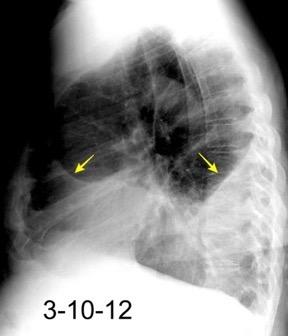

Tb con paquipleuritis calcificada, Hidroneumotórax. Cavidad apical conectada a pleura. Atelectasia redonda

Eyler WR et l. Rib enlargement in patients with chronic pleural disease . AJR 1996